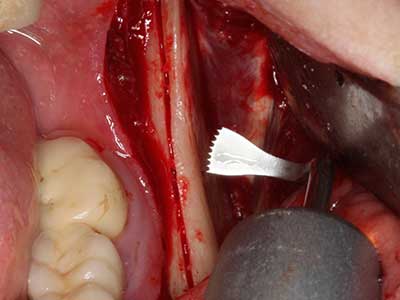

Фиг. 3: Базалното разделяне на блока е по-лесно със специалните извити накрайници.

Фиг. 4: Допълнителни автогенни костни стърготини се събират със скалер за кост.